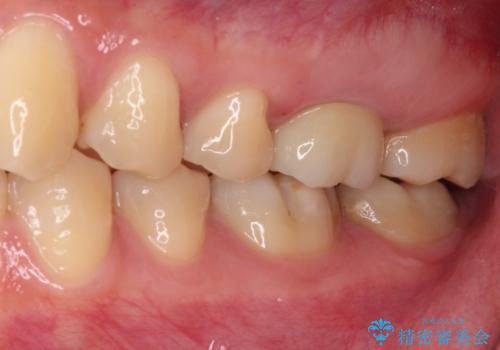

目立つ銀歯がなくなり、患者様は大変満足されました。